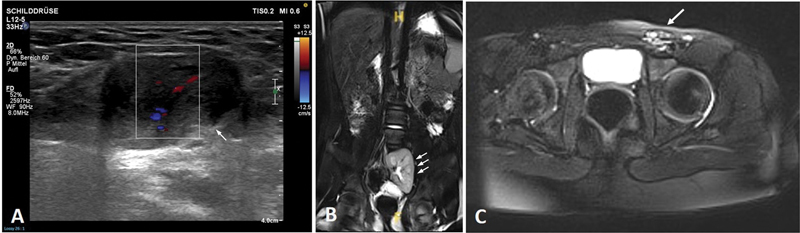

A 12-year-old girl presented with inguinal swelling and recurrent groin pain since menarche. Ultrasound showed an inguinally located ovary with normal perfusion. Herniorrhaphy revealed an ectopic inguinal left ovary with fallopian tube and atretic hemiuterus and a closed internal inguinal ring. Laparoscopy revealed a right-sided hemiuterus and vaginally palpable cervix, leading to the diagnosis of ectopic OHVIRA syndrome type 1.2. The left hemiuterus was resected and the left ovary was pulled through the inguinal canal into the abdomen. During 12 months of follow-up, the left ovary showed normal perfusion and sonomorphologic appearance, menstrual periods were uneventful.